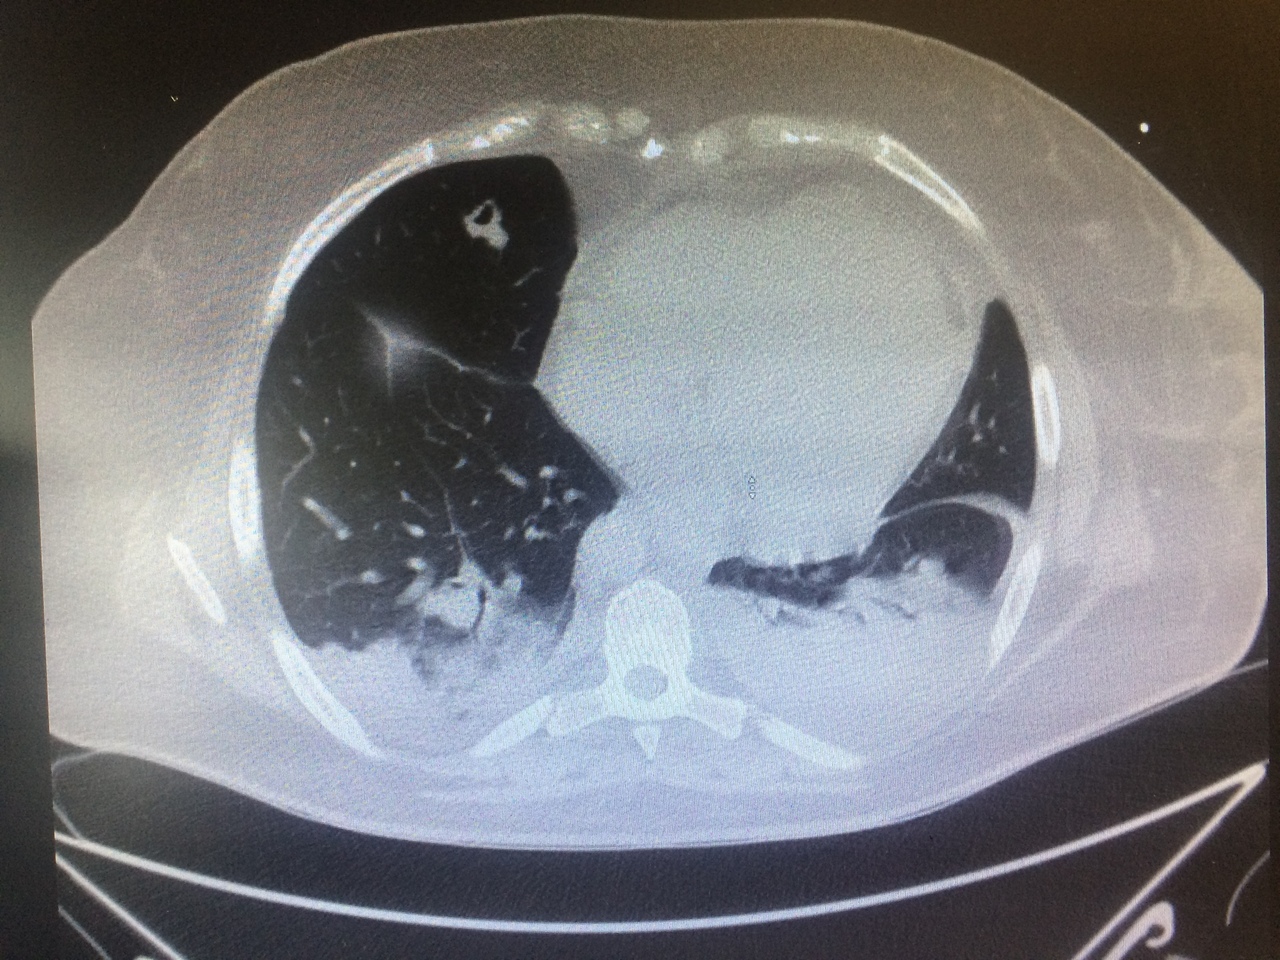

Voici les images du scanner thoracique.

Question 11 : Quelle est votre suspicion diagnostique ?

Syndrome septique chez un porteur de valve prothétique pulmonaire, examen direct suggérant un sepsis à staphylocoques (germe pourvoyeur d’EI), nombreux emboles pulmonaires excavés